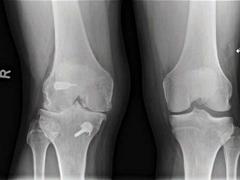

Beschermt een voorstekruisbandreconstructie tegen artrose van de knie? Lees meer over Beschermt een voorstekruisbandreconstructie tegen artrose van de knie? Beschermt een voorstekruisbandreconstructie tegen artrose van de knie?

Letsels van de voorste kruisband (VKB) komen meestal voor bij pivoterende sporten zoals voetbal, hockey, korfbal en zaalsporten. Patiënten krijgen vaak het advies om de VKB te laten reconstrueren omdat ze anders slijtage van de knie krijgen. Het ontstaan van knie-artrose (gonartrose) na een VKB-ruptuur is echter een multifactorieel proces. Wetenschappelijk onderzoek toont aan dat het risico op röntgenologische artrose van de knie gelijk is bij patiënten met en zonder reconstructie van de VKB. De in de praktijk vaak gemaakte opmerking ‘U moet uw voorste kruisband laten reconstrueren, anders krijgt u slijtage van de knie’ is onjuist. Indicaties voor een VKB-reconstructie van de knie zijn klachten van invaliderende functionele instabiliteit, bij het hechten van een meniscusruptuur en de wens tot pivoterende (sport)activiteiten.